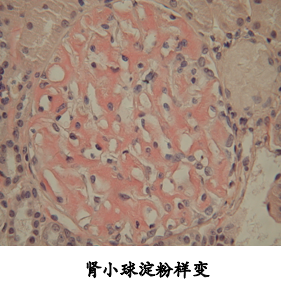

四、淀粉样变性

1.定义:细胞间质出现淀粉样蛋白质-粘多糖复合物沉淀。

2.病变:镜下细胞外间质呈淡红色的均质状。因与淀粉遇碘反应相似故得名(刚果红染色为桔红色,遇碘则为棕褐色,再加稀硫酸便呈蓝色)。

3.常见部位:细胞间、小细管基底膜、网状纤维支架、血管壁。